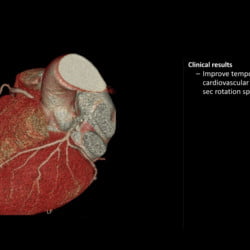

Incisive CT de 64 canais e 128 cortes

Especificações Técnicas do Tomógrafo Philips Incisive CT

| Tipo de tubo | Tubo vMRC Cerâmico |

| Capacidade do tubo | 8 MHU |

| Configuração de kVp | 70, 80, 100, 120, 140 kV |

| Tamanho do bore | 72 cm |

| Cortes | até 128 cortes |

| Cobertura | 40 mm |

| Potência do gerador | 80 kW |

| Velocidade de rotação | até 0,35 s |